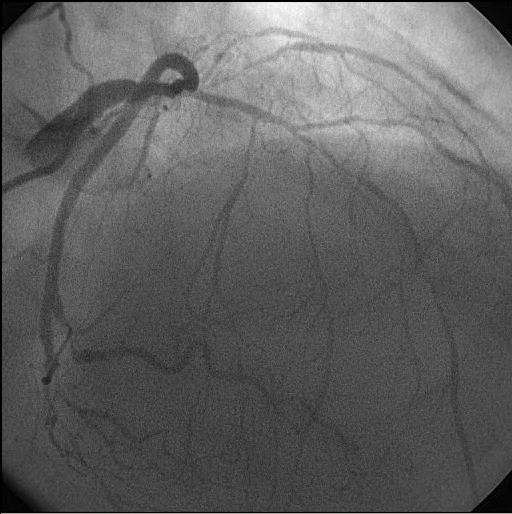

A trifurcation is a division of a mainbranch into three branches of at least 1.5mm. Trifurcations are only scored for the following segment junctions: 3/4/16/16a, 5/6/11/12, 11/12a/12b/13, 6/7/9/9a and 7/8/10/10a.

‘Specify which segments are diseased for lesion X’: one should only fill out those segment numbers of the trifurcation that have a Diameter Stenosis ≥50% in direct contact with the trifurcation.

- One lesion

- Trifurcation: ‘Yes’

- 1 diseased segment involved (= segment no.5).